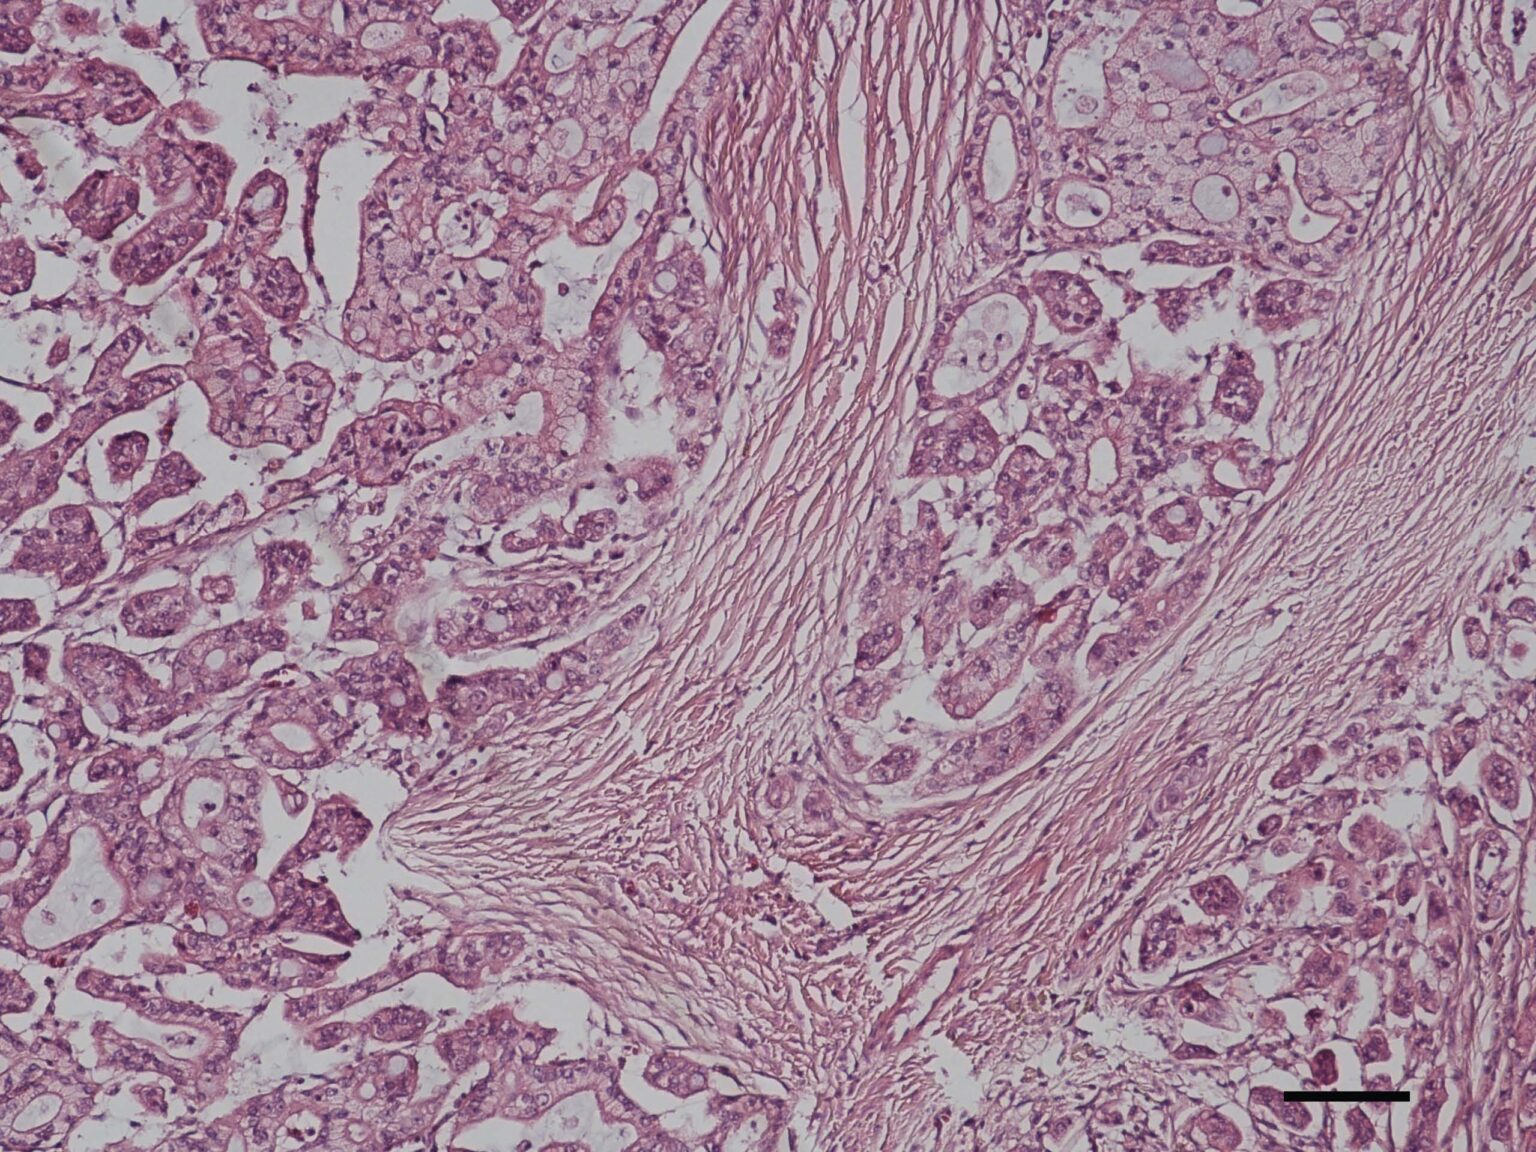

Veterinary Sciences Free FullText Comparative Aspects of BRAF Braf Mutation Hund Laboklin Es handelt sich hierbei um eine somatische. Plos one 2015b, 10(12):e0144170) identified the braf variant. Braf mutation testing is a highly specific method ( 100%) for the detection of canine transitional cell and. Braf mutation in canine transitional cell carcinoma in 2018, we succeeded in establishing the method for detecting braf mutation in tcc. An einer vielzahl von tumoren des. Braf Mutation Hund Laboklin.

Veterinary Sciences Free FullText Correlation of BRAF Variant Braf Mutation Hund Laboklin An einer vielzahl von tumoren des hundes untersucht. Es handelt sich hierbei um eine somatische. Plos one 2015b, 10(12):e0144170) identified the braf variant. Braf mutation testing is a highly specific method ( 100%) for the detection of canine transitional cell and. Braf mutation in canine transitional cell carcinoma in 2018, we succeeded in establishing the method for detecting braf mutation. Braf Mutation Hund Laboklin.